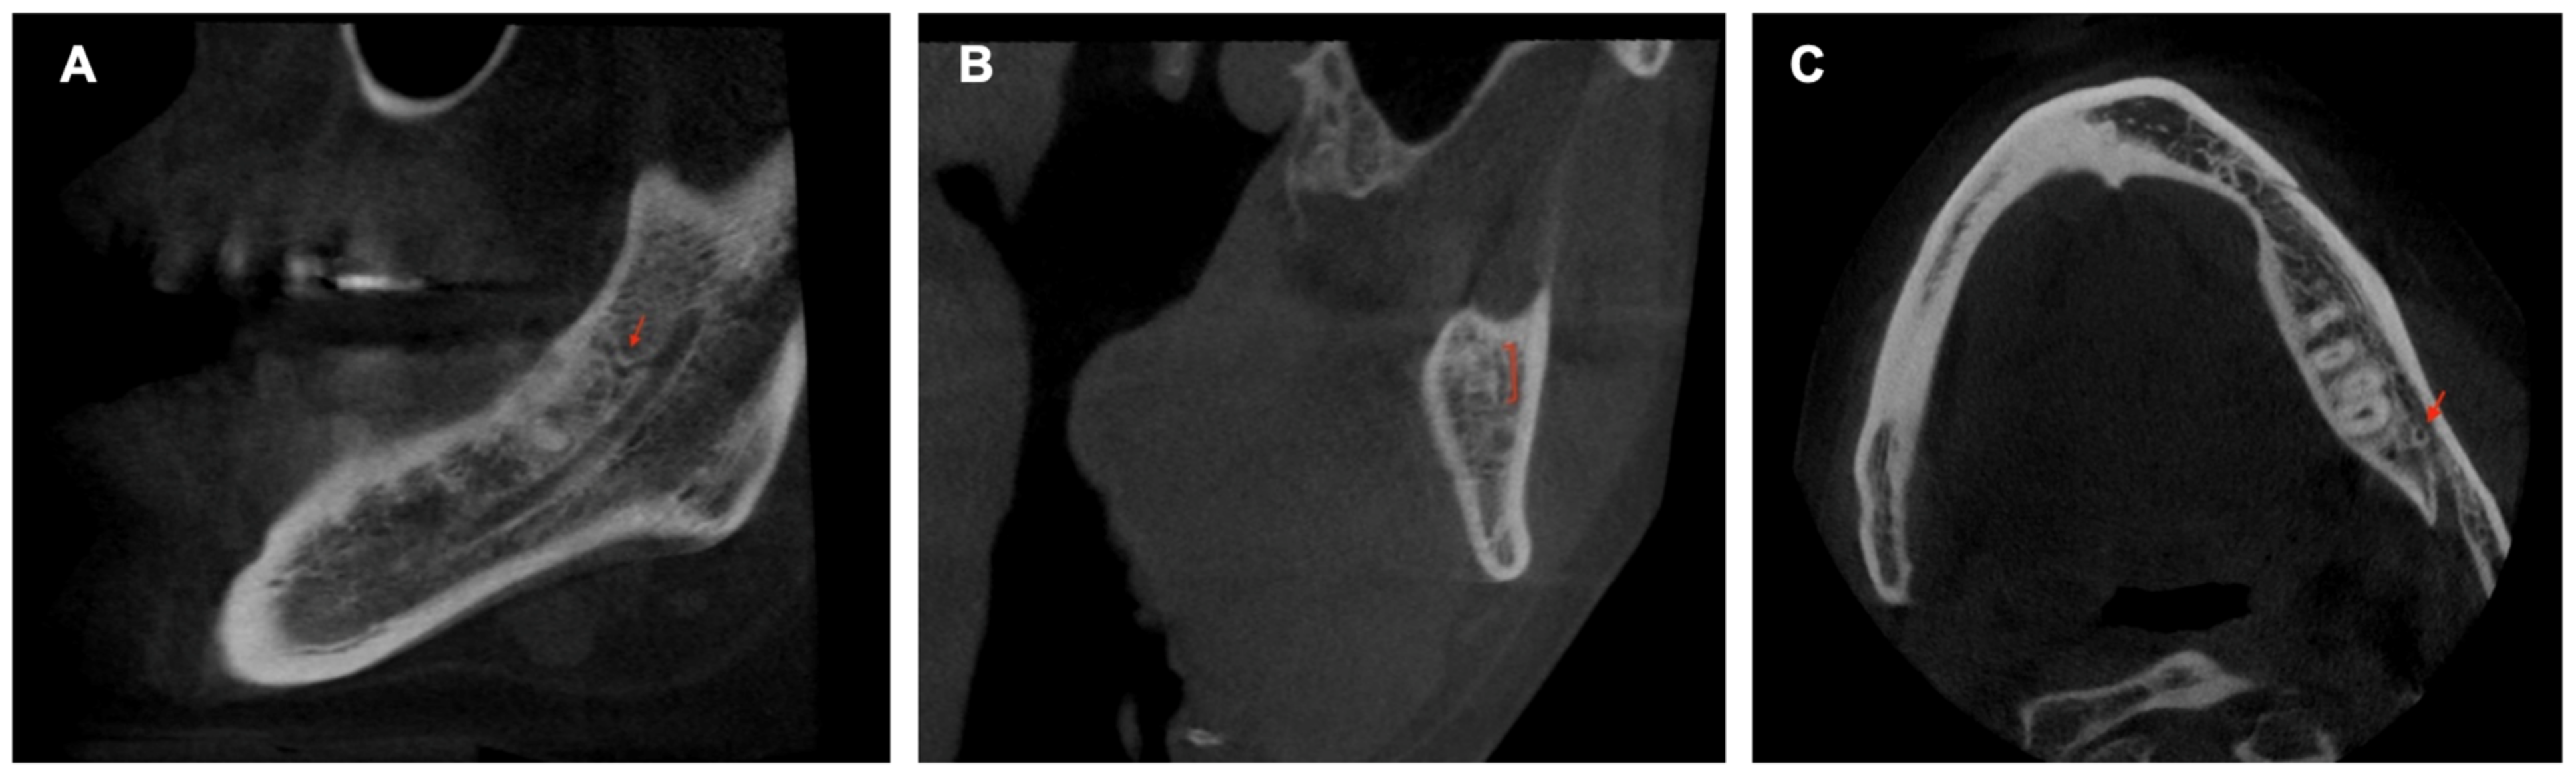

The CBCT study permits longitudinal and oblique rotation of the sections, as well as buccolingual and posteroanterior movements. It was possible to view and analyze the anatomical variants, such as the AL and the RC, using these movements. Once the structures had been identified, their presence was confirmed in every section (Figure 3). The length of the AL was determined by counting the sequential coronal sections from the anterior edge of the MF to the disappearance of the AL, multiplied by the thickness of the section (0.5 mm) (Figure 4).

Figure 4. Cross-sectional CBCT reconstruction. The anterior loop is visible in images No. 11–19 (red arrows). The length was measured as 9 × 0.5 = 4.5 mm. In image No.18 (highlighted with an orange square), the junction of the loop with the mandibular canal is observed, making the canal appear ‘wider’.